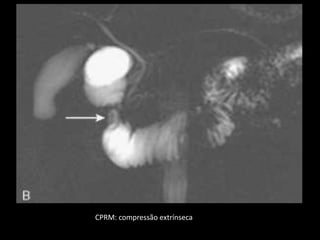

T1: tecido pancreático ao redor da segunda porção

CPRM: compressão extrínseca